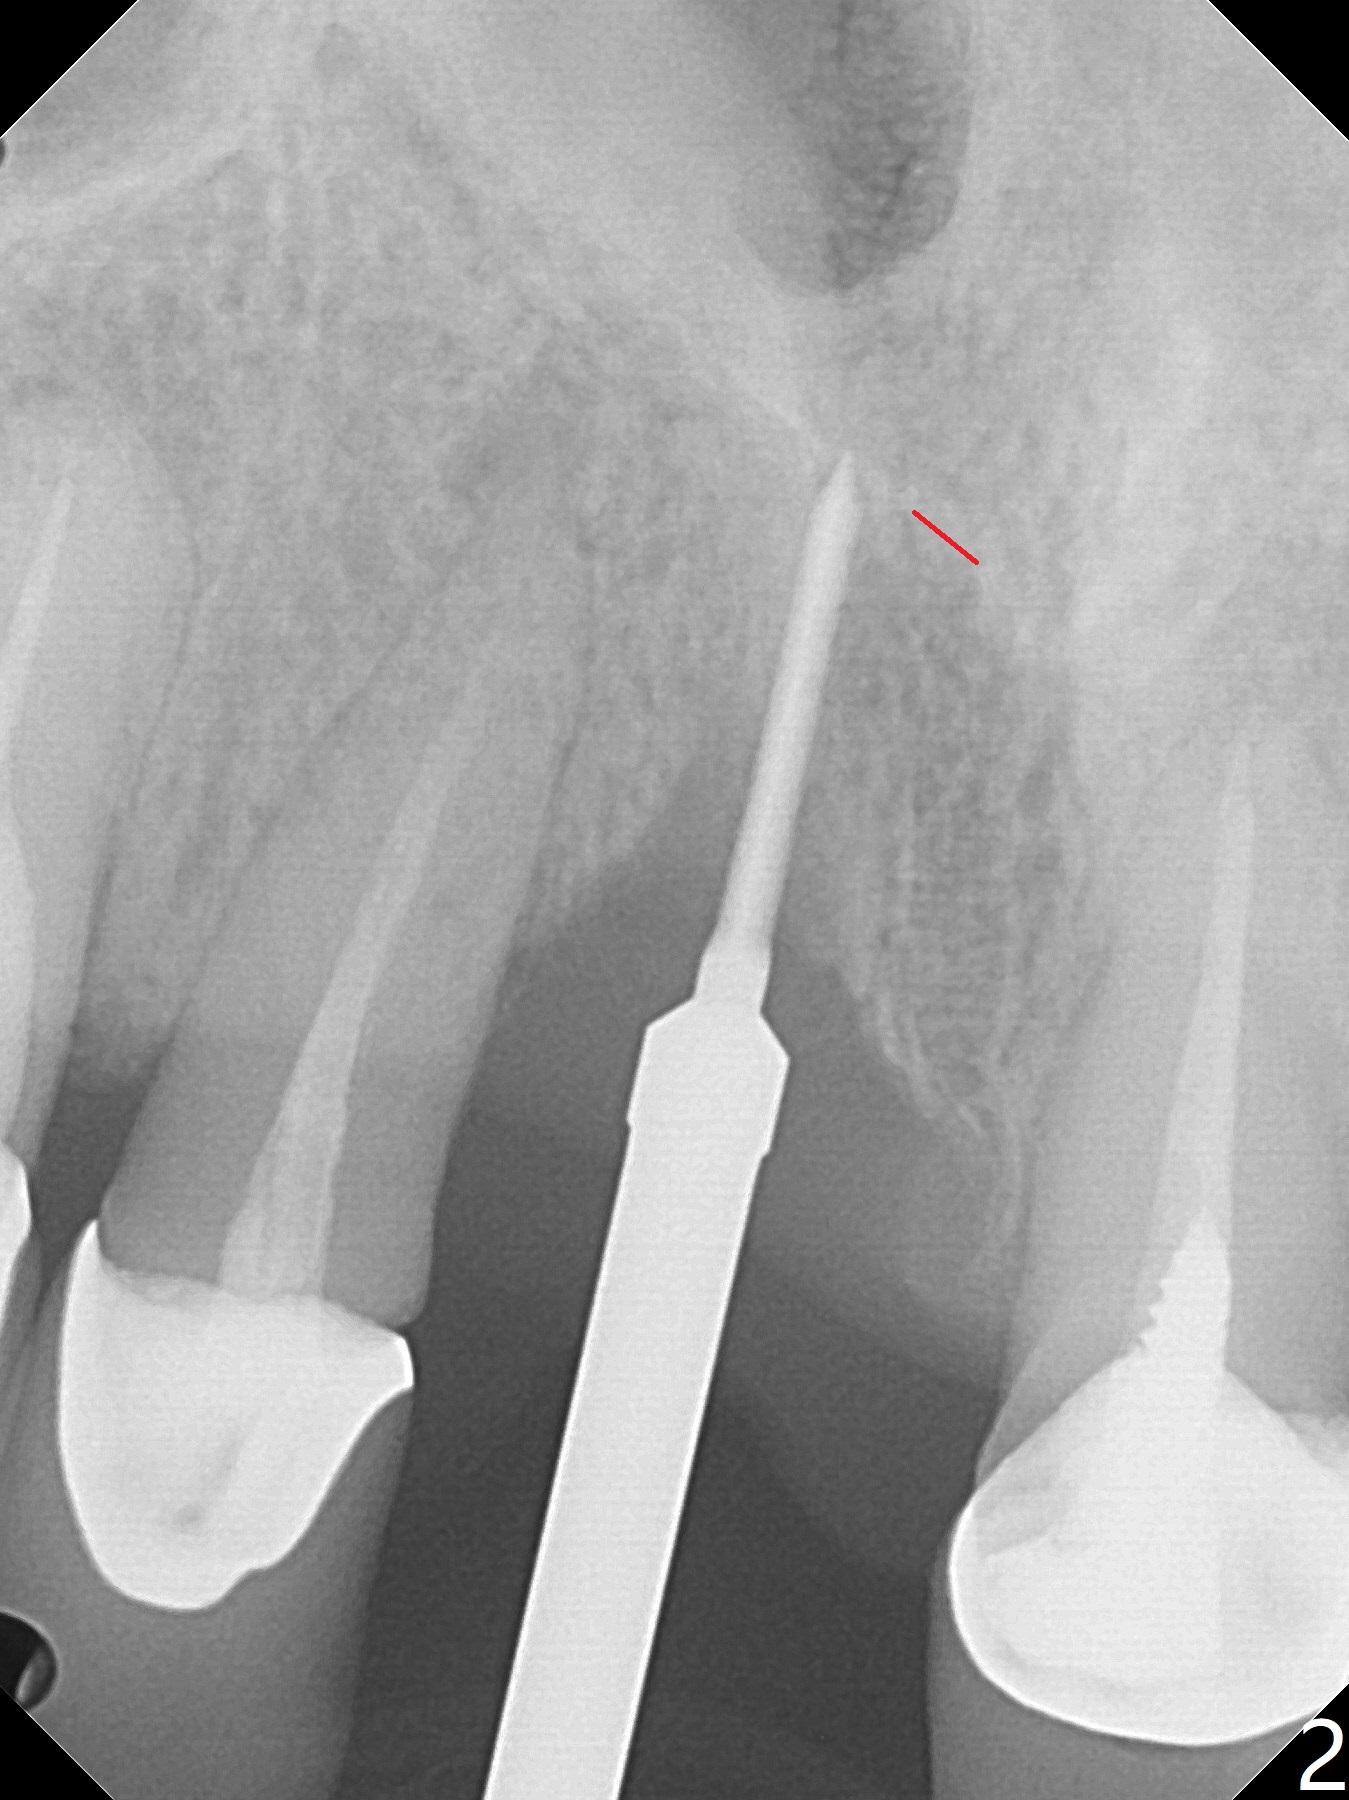

徒手初步钻洞显示方位不对(图一),重新钻洞方位尚可,好像接近鼻底(图二:红线);植入3x11.5毫米一段式植体(图三),3-5个螺纹暴露,植体似乎接近鼻底;旋转植体三趟,植体仿佛卡人鼻底,扭力大约35Ncm,植入粘性骨粉(图四,五:*)前,塞入PRF膜,紧贴颊侧粘膜,促进瘘道愈合。骨粉不仅围绕植体,而且紧贴邻牙牙根(图六(第二轮植骨:overgrafting):<)。病人术后第二周开始使用水牙线,术后三周牙龈健康多了,瘘道消失(图七)。术后六周颊侧骨壁开始塌陷(图八:>),临时牙冠颊侧颈部显得隆起(*)。调整后,牙冠外形改善(图十一至十三),取模前颊侧牙龈缘有可能下降,两个中切牙龈缘可能一致。术后3.5个月骨粉形态(图十四)与术后即刻(图六)有所不同。颊侧牙龈仍红肿轻度触痛(图十五),可能因为临时牙冠不利于局部卫生,所以决定取模制作永久性牙冠。粘固时使用临时胶水,并且涂抗菌素。另外一个可能因素是颊侧骨板薄(图十六:*),细菌感染植体螺纹,永久性牙冠粘固前,拍摄CT(放置cotton roll),必要时,植骨。永久性牙冠远中有缝隙,为了预防病人后悔,使用临时性粘固剂固定(图十七)。Return to No Caries DIO 下一个病例 一段式植体边缘制备 导板与内提升 Xin Wei, DDS, PhD, MS 1st edition 12/22/2020, last revision 06/15/2021